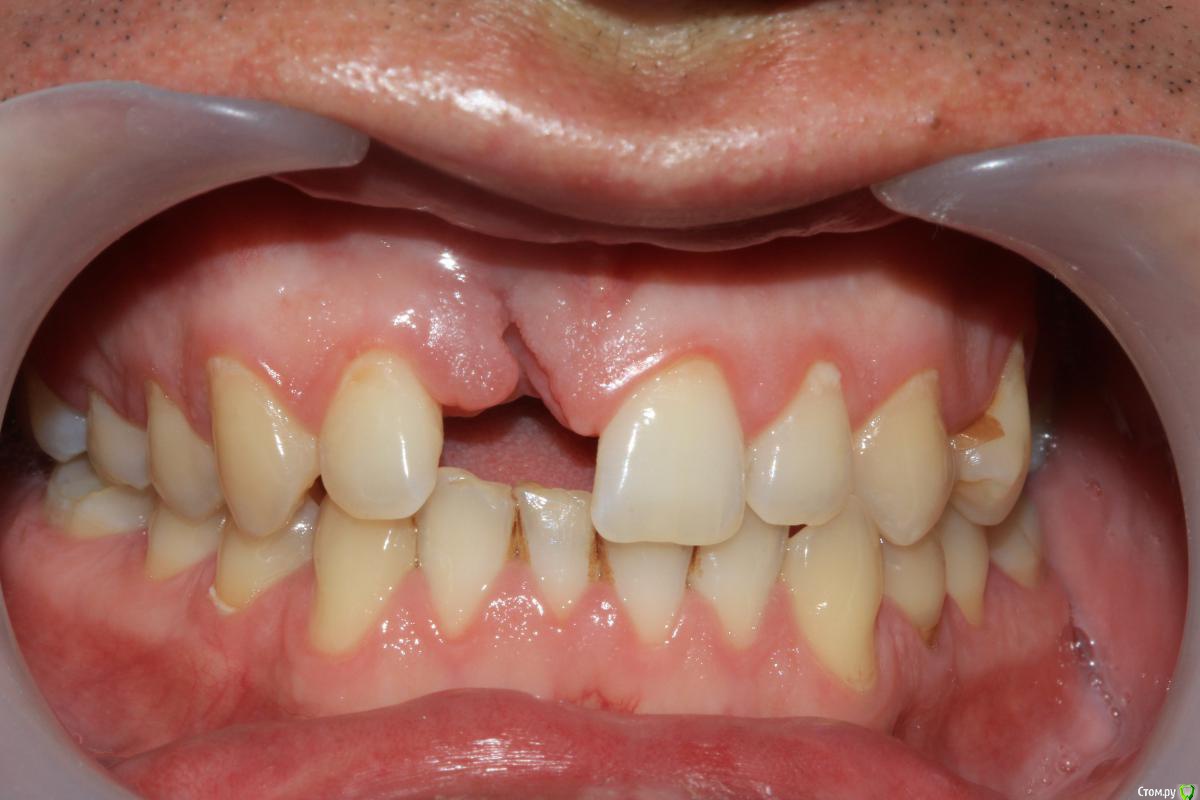

Dc.Petrov Опубликовано 4 мая, 2016 Поделиться Опубликовано 4 мая, 2016 Травма около 2 мес назад + травматичное удаление. Итог на фото.12 неподвижен. Вопрос : удастся ли с помощью нкр сделать кость для имплантации? Ссылка на комментарий

Большой Зеленый Опубликовано 4 мая, 2016 Поделиться Опубликовано 4 мая, 2016 12 придется удалить. 8 Ссылка на комментарий

Dc.Petrov Опубликовано 5 мая, 2016 Автор Поделиться Опубликовано 5 мая, 2016 (изменено) медиального пика у 12 нет однозначно, медиальная поверхность корня визуализируется между складками десны Изменено 5 мая, 2016 пользователем Dc.Petrov Ссылка на комментарий